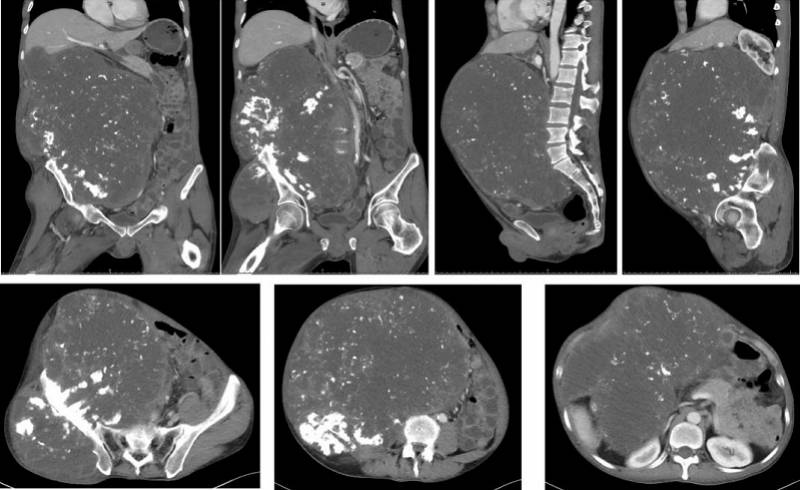

文章图片

CT检查提示 , 老周的肿瘤各个截面的直径都超过30厘米 。